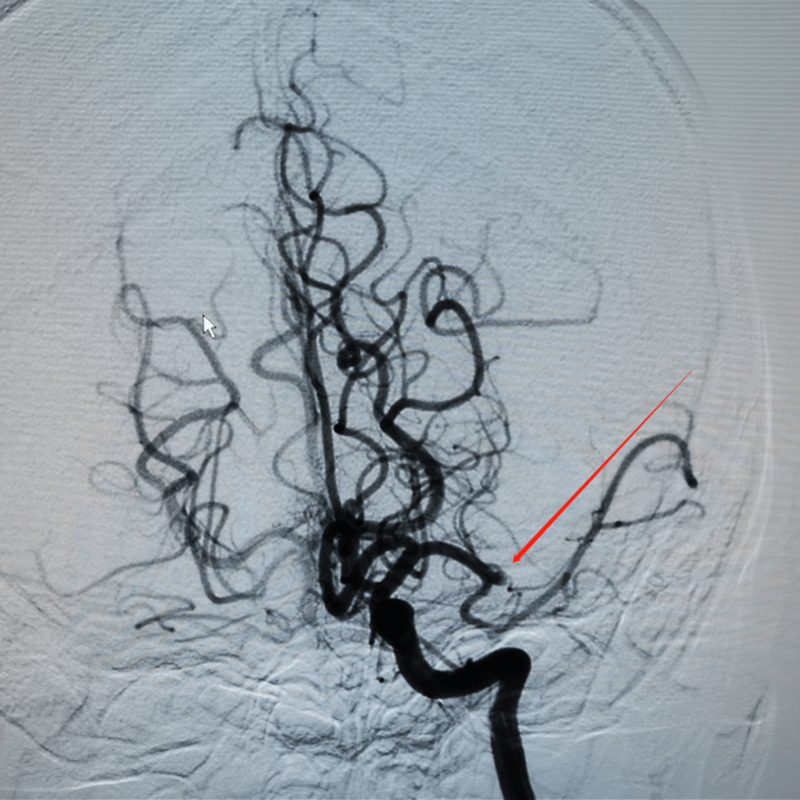

时间就是大脑!为进一步确定左脑缺血原因 , 广医三院神内介入组副主任医师邹卿立即为小张施行了全脑血管造影术 , 证实了血管的闭塞 , 如果不能及时救治将导致其瘫痪!

文章图片

全脑血管造影术 , 可见左侧大脑中动脉闭塞 。

随即 , 神经内科介入团队决定为小张实施介入取栓术 。 值得庆幸的是 , 家属送医还算及时 , 左侧大脑的动脉复通 , 闭塞的血管再次恢复了血流 。